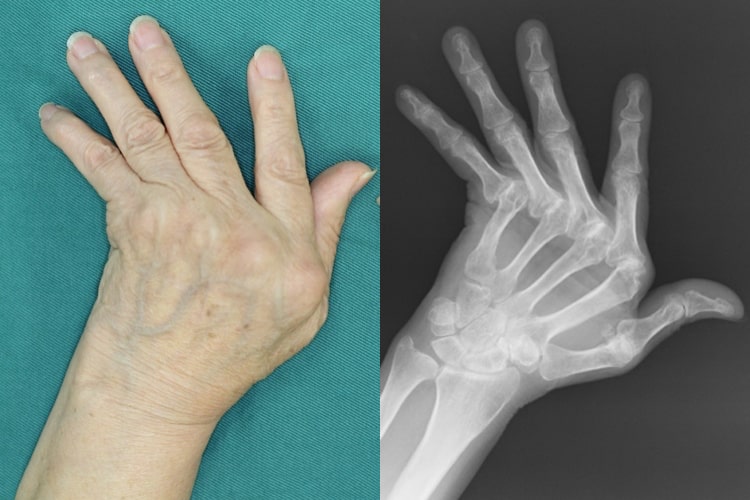

関節リウマチ

リウマチ術前写真

術前

リウマチ術後写真

人工指関節置換術後

原因

関節リウマチにより手や指、肘の関節が破壊されて変形や疼痛が生じます。滑膜炎により指の腱が切れてしまうこともあります。関節リウマチの治療の基本は内服加療ですが、骨破壊が生じてしまったり、腱が断裂した場合は手術が必要です。

症状

手や指、肘の変形、痛み、腫れが出現します。突然指が伸びなくなったりすることもあります。

治療方針

腱が切れた場合は腱移行や腱移植を行って治療します。手の腫れや痛みが持続した場合、関節破壊の程度に合わせて滑膜切除、関節形成、関節固定を追加します。最近は人工手関節置換術を行う場合もあります。指や肘の関節リウマチについても、腫れや痛みが持続する場合は人工関節置換術を行うことで生活レベルの向上が期待できます。